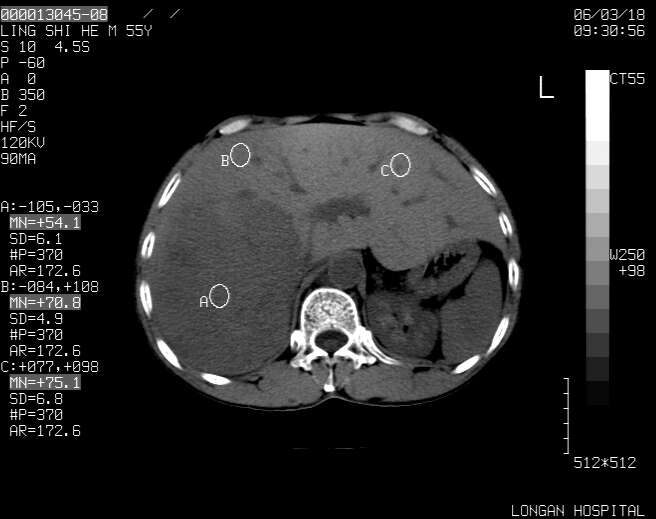

以下是引用guzhongliangddd在2006-3-21 22:13:00的发言:[br]病灶主要位于肝右叶的后份,内见异常血管,门脉主干及右支受侵{提示有癌栓形成},门腔间隙内见增大淋巴结。肝左叶内未见异常。

以下是引用zhuxinli在2006-3-22 1:23:00的发言:[br][br] 病灶主要位于肝右叶的后份,内见异常血管 .门脉右支截断,右叶前段早期强化(考虑动静脉漏),腹膜后肿大淋巴结,病灶逐渐强化,考虑为胆管细胞癌[br]